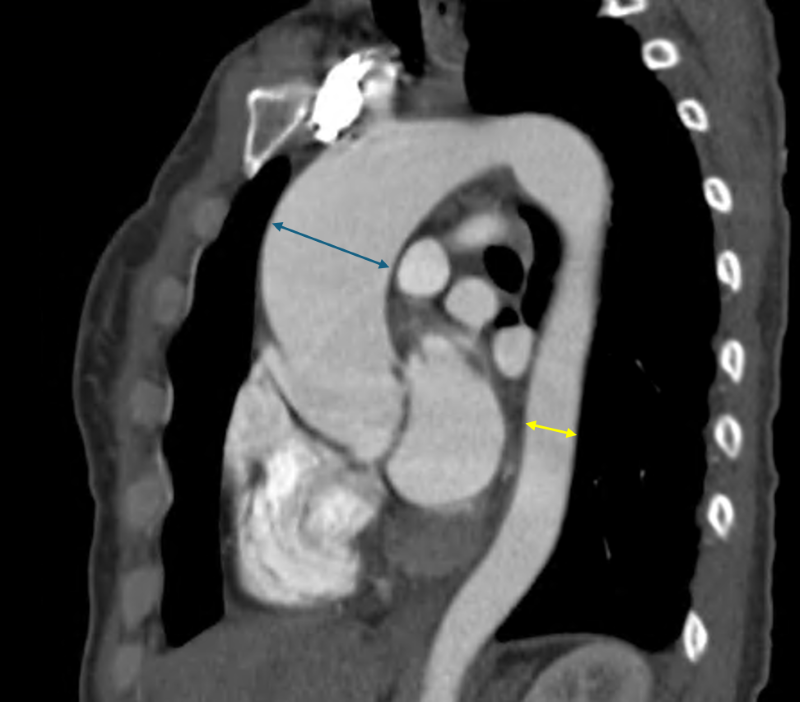

藍色箭頭部分為近五公分大的主動脈瘤,黃色箭頭為相對正常的主動脈大小。

一般而言,重度主動脈瓣膜狹窄多見於70歲以上病人,而如陳女士般尚未50歲就發生嚴重鈣化與狹窄的多是先天性雙瓣的主動脈瓣者。先天性雙瓣主動脈瓣膜的患者在中年即容易出現瓣膜狹窄或閉鎖不全,並伴隨主動脈擴大的問題。國外統計指出,約有40-60%的雙瓣主動脈瓣患者會出現主動脈瘤或主動脈擴大情形。

重度主動脈瓣膜狹窄的病人,唯一治療方式就是開刀置換主動脈瓣,無法僅靠藥物控制。目前的手術方式有開心手術與經鼠蹊部導管置換主動脈瓣手術兩種,由於上述病人合併有主動脈瘤且不符合後者的健保適應症,醫療團隊以開心手術的方式替其治療。特別的是,傳統開心手術需劈開整塊胸骨,傷口可達15至20公分,但採J型鋸開胸骨,以僅約6公分的傷口,將已經鈣化的瓣膜組織完整切除,接著處理主動脈內部殘留的鈣化區塊,進行去鈣化和壓碎處理。之後,植入一枚新的人工生物瓣膜。同時,將動脈瘤的部分一併切除,再以手縫方式接上人工血管,完成修復。